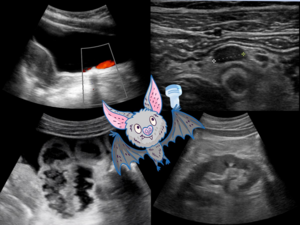

Grundkurs Notfallsonographie 06. & 07.06.2026

Sonographie ist als diagnostisches Instrument aus der Notfallmedizin nicht mehr wegzudenken. Non-invasiv, rund um die Uhr verfügbar und kostengünstig lassen sich mit ihrer Hilfe zeitkritische Diagnosen stellen – oder ausschließen. Auch notfallmäßige therapeutische Interventionen wie die Anlage von Drainagen oder Gefäßzugängen können sonographiegestützt schnell und sicher erfolgen. Allerdings setzt dies ein erhebliches Maß an technischem Know-How, praktischem Geschick und klinischer Erfahrung voraus. Um im komplexen Setting eines klinischen Notfalls belastbare sonographische Diagnosen stellen und die Entscheidung für oder gegen therapeutische Maßnahmen darauf stützen zu können, müssen die sonographischen Untersuchungsabläufe von Thorax, Abdomen, Retroperitoneum und Gefäßen daher systematisch erlernt und eingeübt werden.

Das hierfür angebotene, interdisziplinär ausgerichtete Kurskonzept setzt das Curriculum des Arbeitskreises Notfallsonographie der DEGUM um (www.degum.de/fachgebiete/arbeitskreise/notfallsonografie.html).

Der Leitgedanke der Basisausbildung Notfallsonographie ist die symptomorientierte Strukturierung und Priorisierung der sonographischen Untersuchung im Notfallsetting. Damit ist dieses Format besonders für die Vorbereitung auf Tätigkeiten in allen akutmedizinischen Bereichen (z. B. Notaufnahme, Intensivstation, prähospitale Notfallmedizin) geeignet.

Der zweitägige Kurs ist entsprechend von der DEGUM als Grundkurs Notfallsonographie (Teil 1 + Teil 2)

zertifiziert und wird zudem als DEGUM Anästhesie „Grundkurs 2“ anerkannt. Darüberhinaus ist die Veranstaltung von der Ärztekammer Nordrhein als ärztliche Fortbildung anerkannt und für Notärztinnen und Notärzte anrechenbar gem. § 5 Abs. 4 RettG NRW.